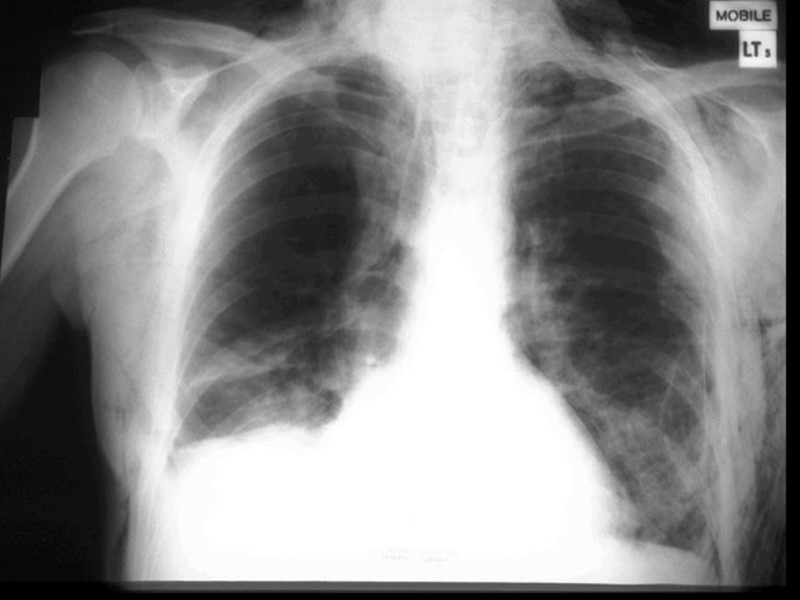

Травматический разрыв аорты Рентгенологические признаки Широкое средостение Переломы в 1 и 2 ребрах Облитерация аортальной выпуклости Девиация трахеи направо Плевральная шапка Снижение левого главного бронха Подъем и отклонение правого главного бронха Облитерация “aoртального окна” Отклонение пищевода направо